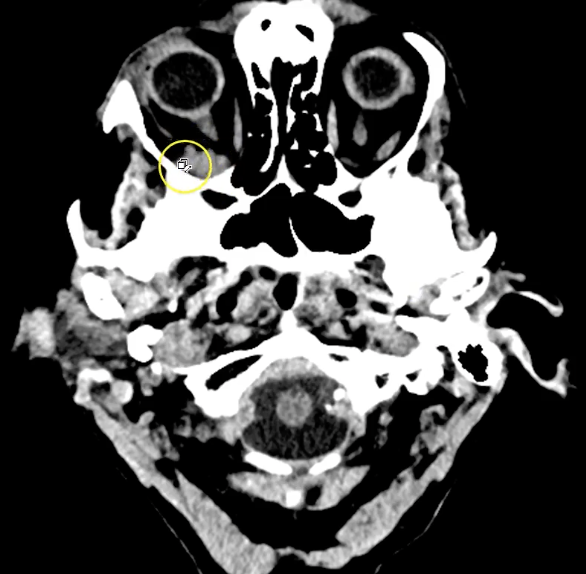

term image

right retroorbital mass. 8mmx9mm puts force on R orbital nerve